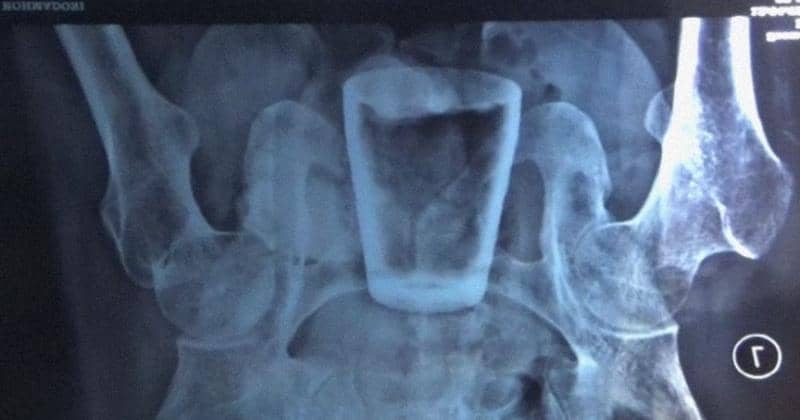

Nurlasiadi kemudian melakukan rontgen untuk mengetahui penyakit yang diderita. Ternyata di dalam perutnya terdapat gelas kaca. Ukurannya kurang lebih 8 cm dengan diameter sekitar 3 cm, bahkan bentuknya pecah sebagian.

5. Menurut Doddy, posisi gelas berada pada bagian rektum anus

"Jadi bukan perut tengah, tetapi dekat dengan anus atau dubur, saat foto rontgen ada benda asing (gelas) itu. Sehingga penanganan operasinya, (bagian) anusnya di robek (sedikit) supaya bisa mengambil gelasnya. Bukan dilakukan operasi pembedahan besar diperut," jelasnya.